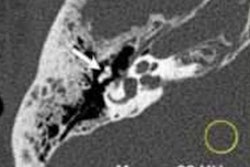

Reference protocol (top) and evaluated protocol (bottom) images in a 74-year-old man with multiple myeloma. Soft-tissue reconstruction is shown (left side; window width, 400; window level, 40), whereas the right column is the bone reconstruction (right side; window width, 3700; window level, 600). A lytic bone lesion in the L3 vertebral body is more conspicuous on the noncontrast-enhanced axial photon-counting CT reconstruction images (bottom; solid arrows) compared with the noncontrast-enhanced axial energy-integrating detector CT reconstruction images (top; dashed arrows). Image and caption courtesy of the RSNA.Whole-body low-dose CT has a mean effective dose that ranges between 4 mSv and 8 mSv, but low-dose images can be noisy. Photon-counting CT shows promise for imaging bone disease caused by multiple myeloma because its smaller detector pixel sizes eliminate the need for the high-spatial-resolution filters that conventional CT requires -- which translates not only to better dose efficiency but also less noise.